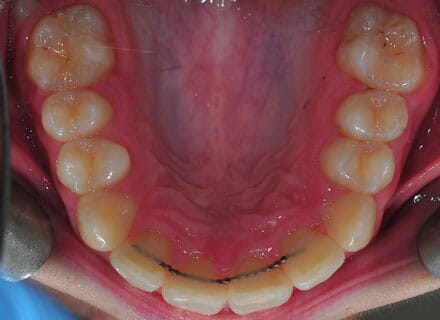

This lady hated her very uneven smile, all the teeth sticking out at the sides, teeth bunched together and uneven. We fitted clear brackets and a wire on the inside in the upper jaw in the roof of the mouth and in under 18 months the teeth were perfectly aligned and the patient’s smile was changed forever.